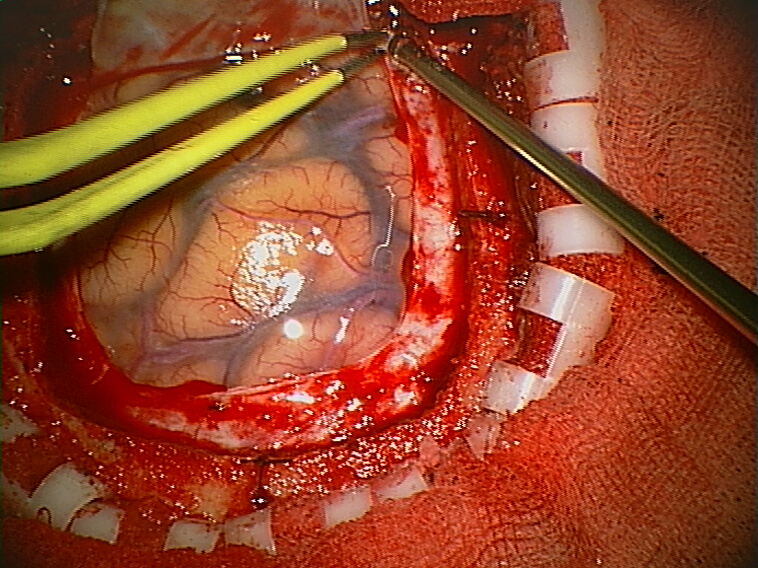

Craniotomy Arachnoid.

Sitting craniotomy.